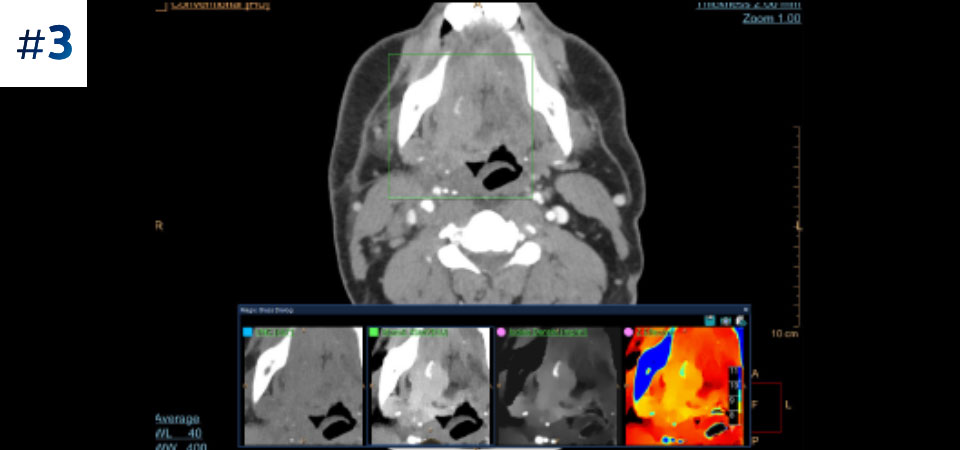

Philips Spectral CT 7500 scanner

Detector-based spectral CT technology

See beyond conventional CT to detector-based spectral CT

With Philips true detector-based spectral CT, scan as you normally would for fast, low-dose conventional and spectral results. Detector-based spectral CT acquires scans within a single exposure and without special protocols, and with results on demand. There’s no need to choose between viewing anatomical structures and identifying material composition. Detector-based spectral CT images capture spectral information 100% of the time, so you can analyze spectral data in any image retrospectively for rich clinical insights. Speed confident diagnosis and minimize the need for additional scans.

Retrospective analysis for results on demand with no trade-offs

With spectral CT, image quality, dose and workflow come together. Perform fast, low-dose spectral scans without compromising speed, power or field of view. Now you can convert deep clinical data into valuable diagnostic information using simple, routine scanning with seamless integration of spectral data into your reading environment for a fast path to diagnosis.